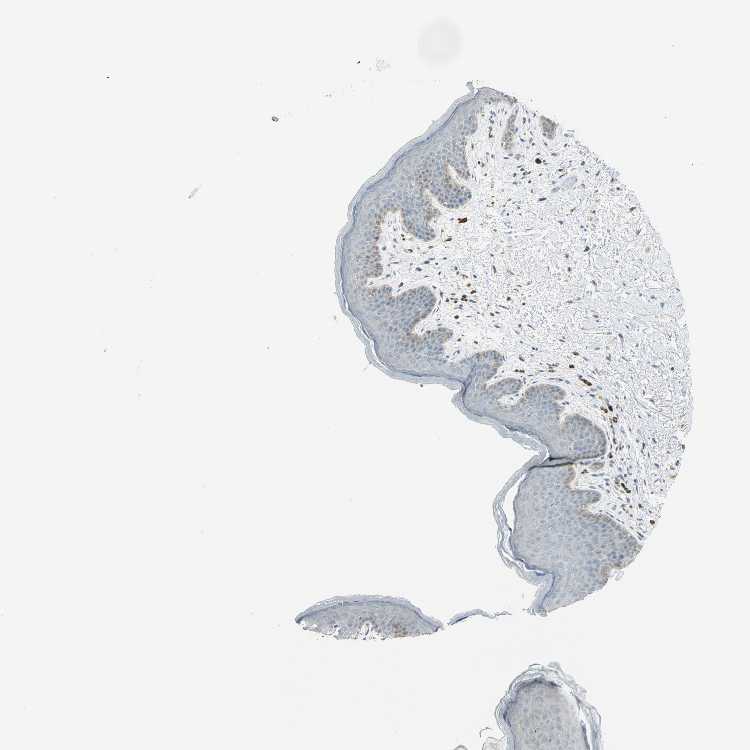

SKIN 1 - Antibody stainingi

Antibody staining in the annotated cell types in the current human tissue is reported as not detected, low, medium, or high, based on conventional immunohistochemistry profiling in selected tissues. This score is based on the combination of the staining intensity and fraction of stained cells.

Each image is clickable and will lead to virtual microscopy that enables deeper exploration of all samples and also displays staining intensity scores, fraction scores and subcellular localization as well as patient and tissue information for each sample.

Antibody HPA005482

Langerhans Not detected

Fibroblasts Not detected

Keratinocytes Not detected

Melanocytes Not detected